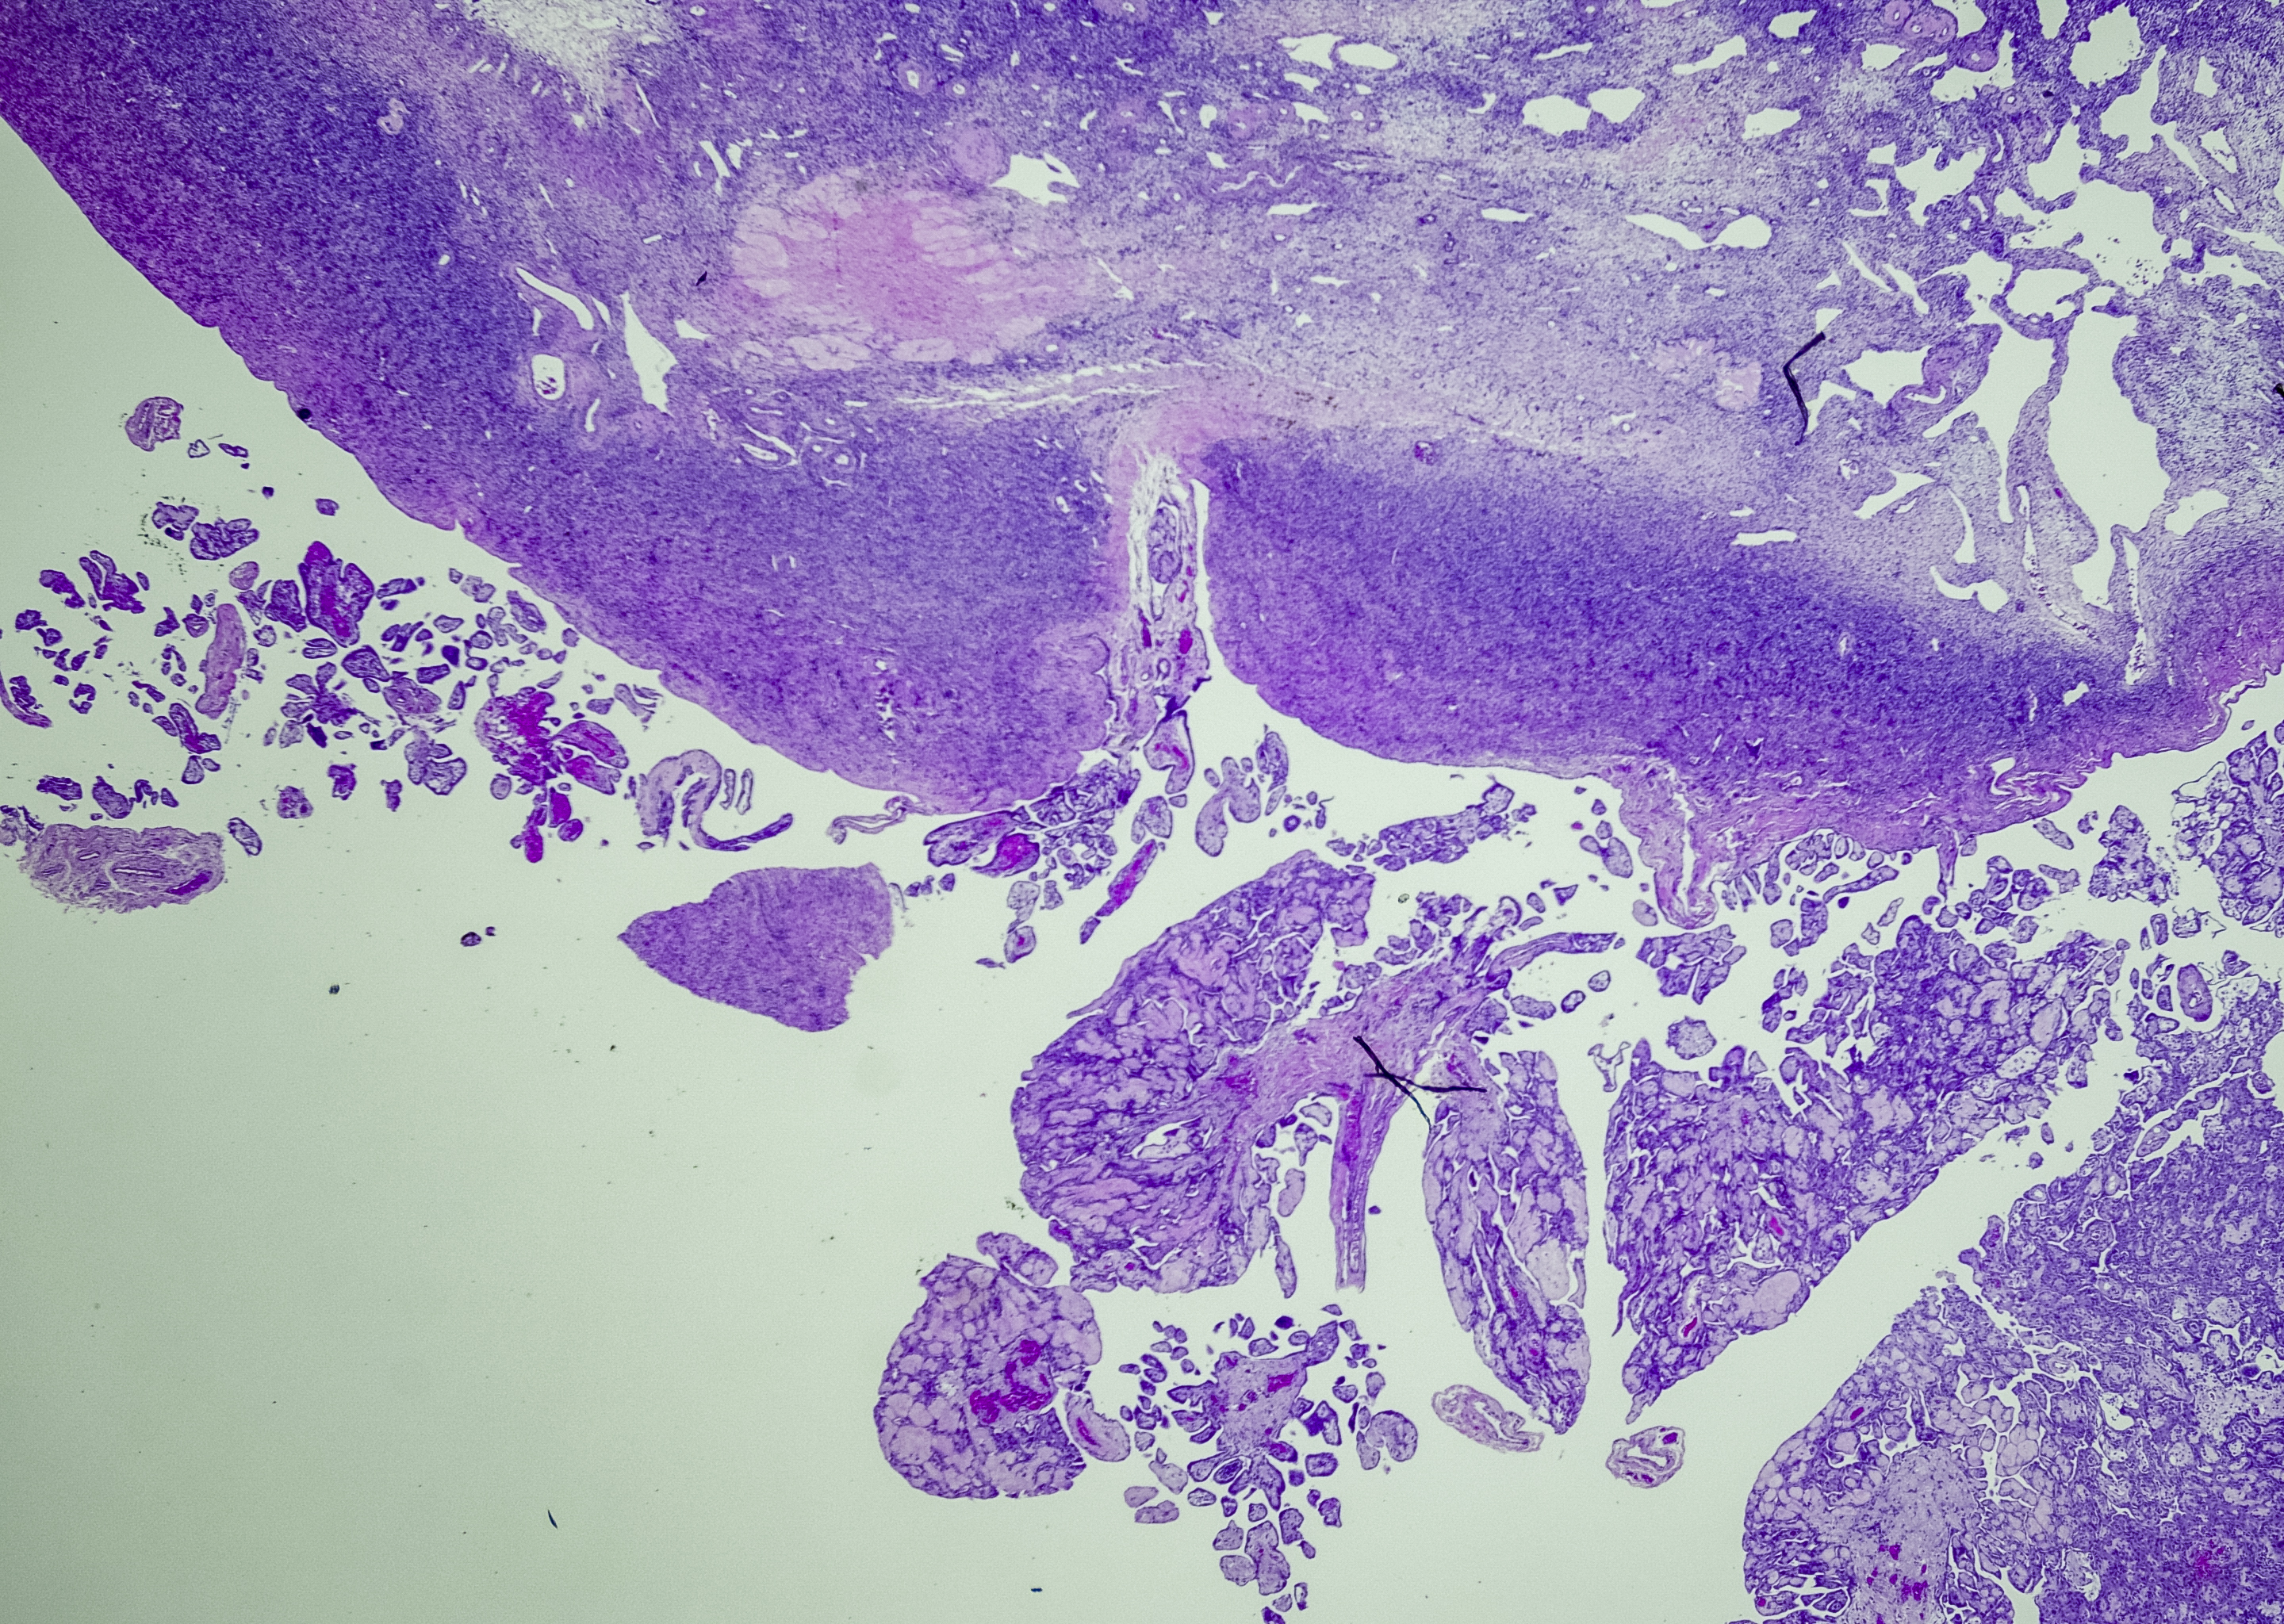

Malignant Mesothelioma is a rare type of cancer that occurs in the thin layer of cells lining the body’s internal organs, known as the mesothelium. Exposure to asbestos is the only recognised cause of this type of cancer, though factors such as smoking can increase the likelihood.

Symptoms include shortness of breath and chest pain, however the disease is usually only detected after the cancer has spread. These cells often spread to other parts of the lung where they form a secondary cancer.